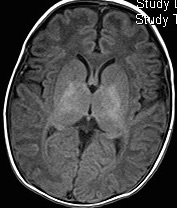

Hypoxic-ischaemic injury to gray matter (thalami and lentiform nuclei) demonstrates characteristic T1 hyperintensity and T2 hypointensity

Neonatal hypoxic-ischaemic encephalopathy (HIE) is the result of a global hypoxic-ischaemic brain injury in a term neonate, usually after asphyxia.

Radiographic features

In term infants blood flow is ventriculofugal and changes are mainly, like in older children, in watershed-border zones; namely, parasagittal grey matter and subcortical white matter. Profound HIE in term babies results in thalamic and basal ganglia as well as sensorimotor cortex (perirolandic region) injury.

MRI

MRI is the most sensitive and specific imaging technique for examining infants with suspected hypoxic-ischaemic brain injury. Conventional sequences can help exclude other causes of encephalopathy such as haemorrhage, cerebral infarction, neoplasms, or congenital malformations.

A number of patterns of injury are encountered (see patterns of neonatal hypoxic-ischaemic brain injury) depending on the stage of brain maturation and severity of asphyxia, with the following expected signal intensity changes:

T1

grey matter: hyperintense

white matter: hypointense

T2

grey matter: variable depending on the time of imaging and presence of haemorrhage

white matter: hyperintense